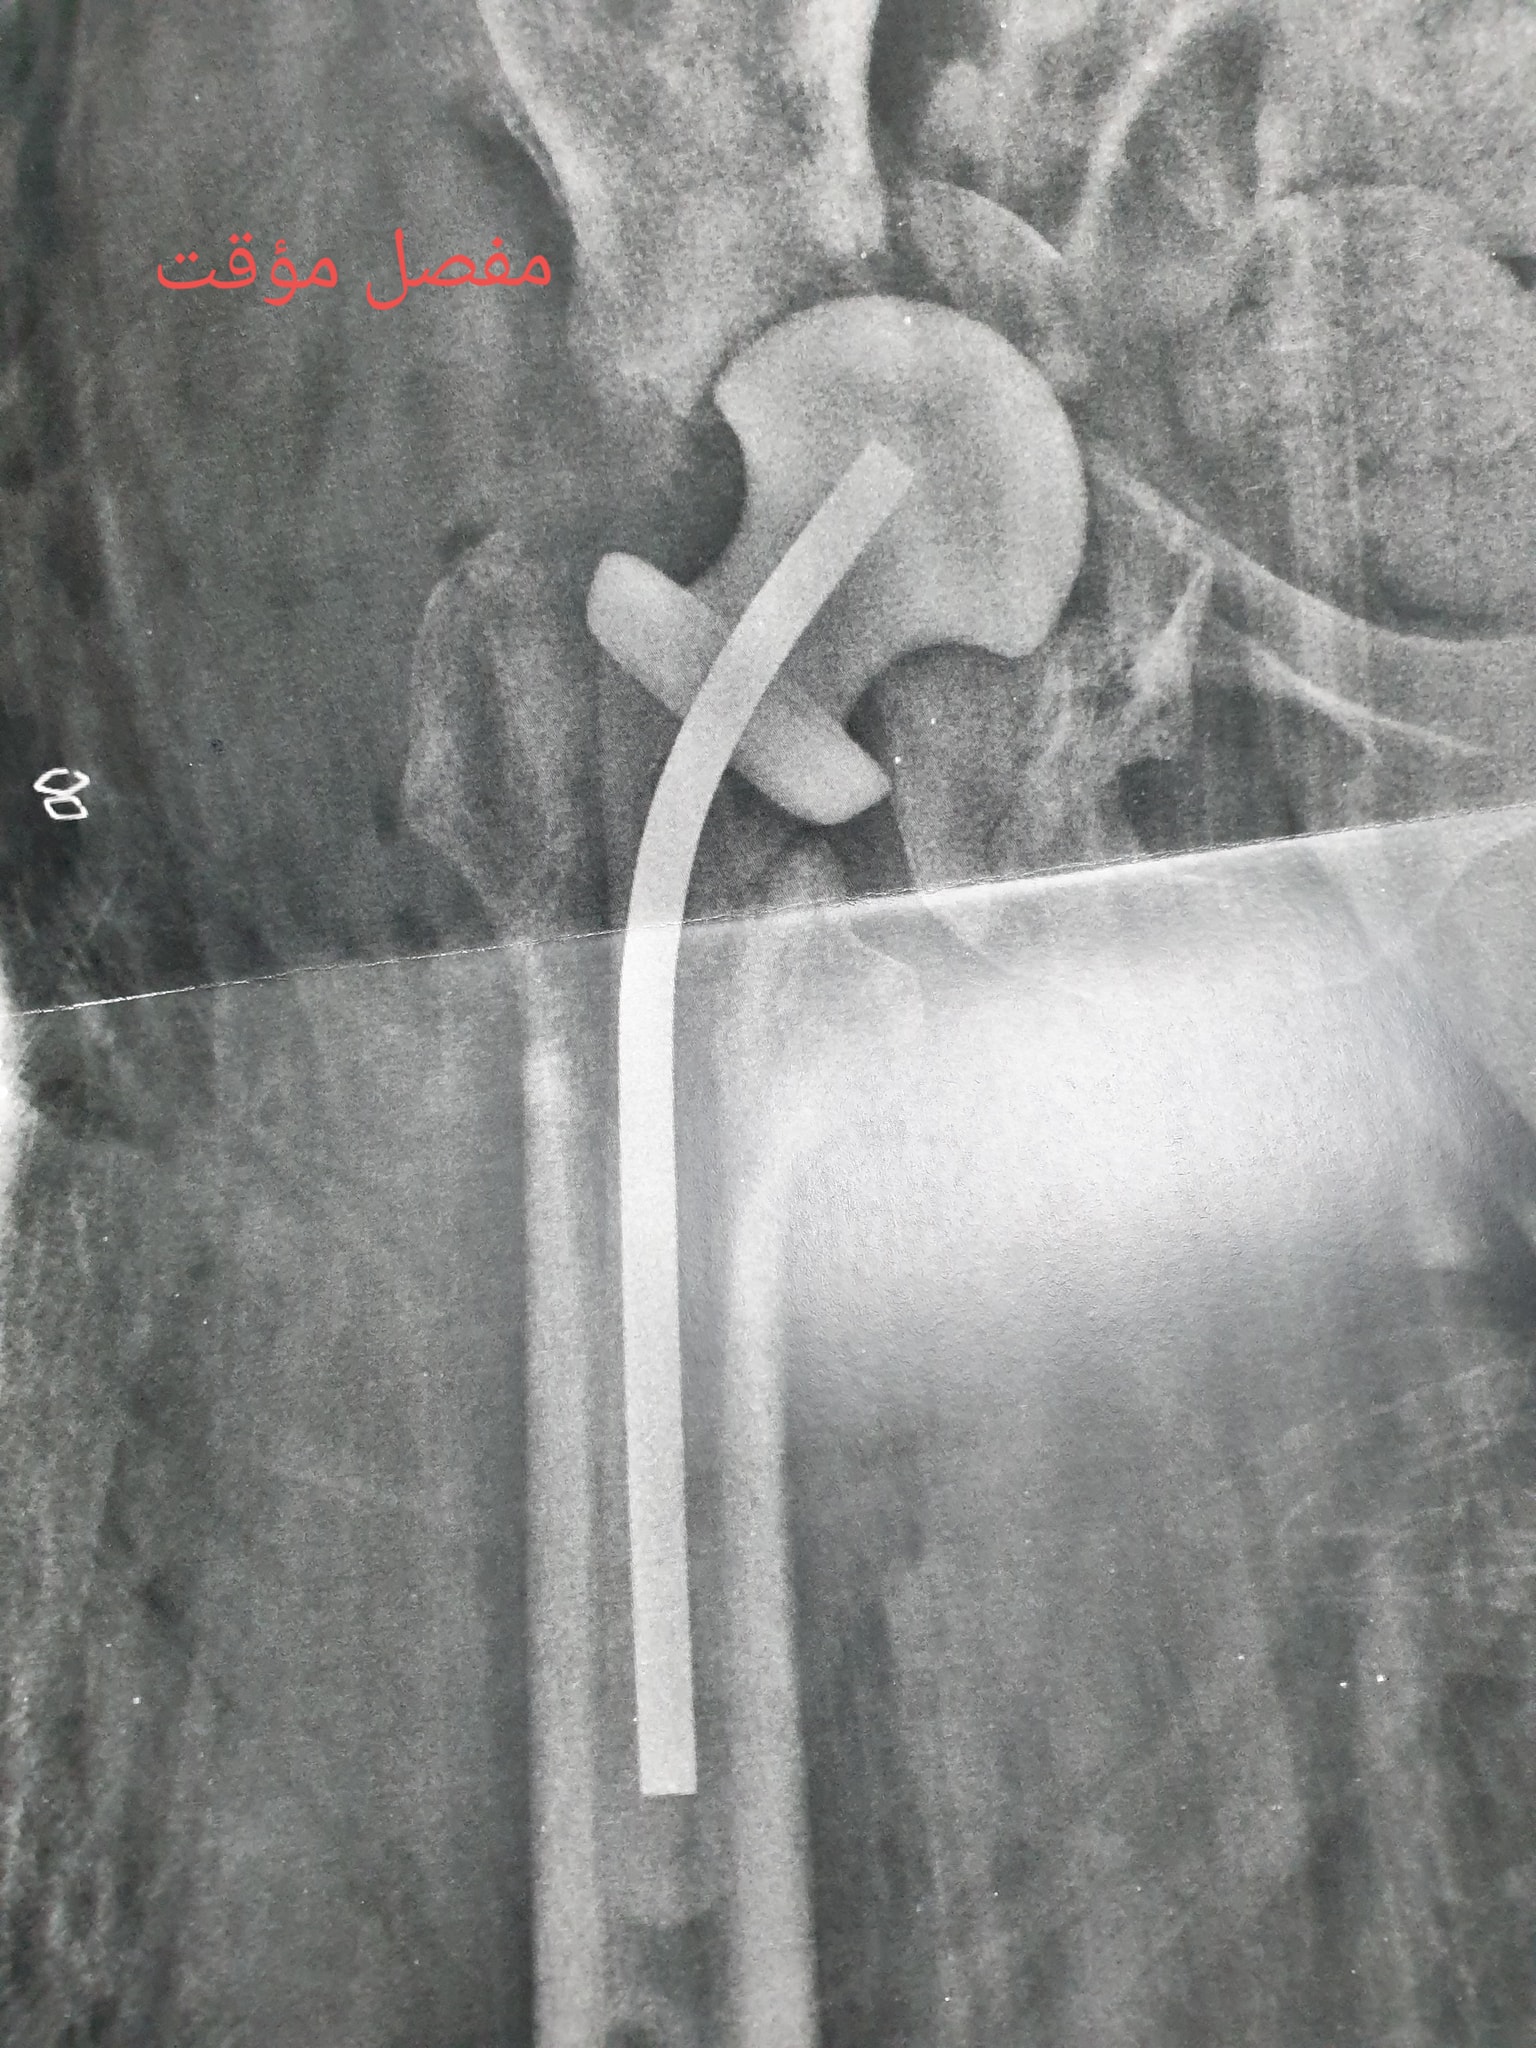

زراعة المفاصل الصناعية ورك و